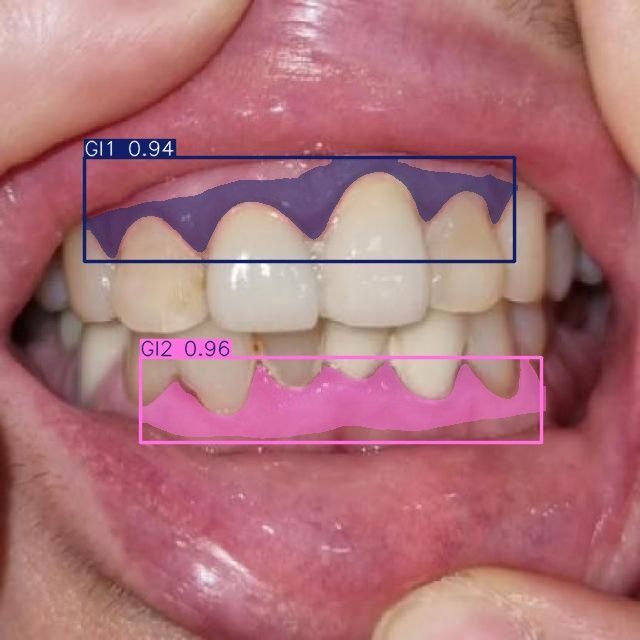

Мы проводим discovery-фазу для нашего клиента (стоматологическая клиника в Москве) и создали работающий прототип ИИ-сервиса, который автоматически сегментирует зубы и связанные патологии по 10 специализированным классам на стоматологических изображениях. Решение построено на Ultralytics YOLOv11-seg, обучено на пользовательском датасете и ускоряется на GPU (CUDA). Прототип уже демонстрирует корректную сегментацию и классификацию по классам кариеса, состояниям десен и показателям пародонта, что открывает путь к автоматизированной диагностике, системам поддержки клинических решений и оценке состояния зубов в реальном времени.

- Состояние десен: G1

- Воспаление десен (гингивит): GI1, GI2, GI3